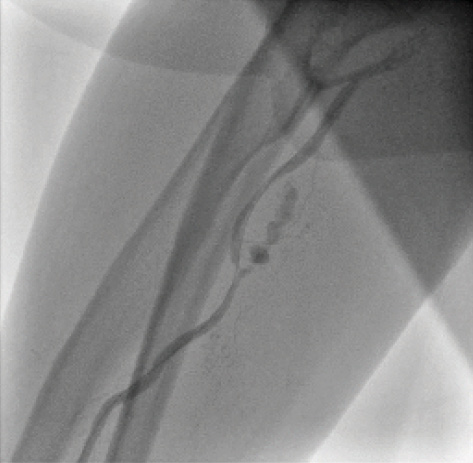

Transradial cardiac angiography and catheterization have been increasingly adopted over the past 10 years in the United States.1 Advantages of this technique include reduced mortality in patients with acute coronary syndrome, decreased vascular complications, shorter length of stay, early ambulation, and the potential for same-day discharge after percutaneous coronary intervention (PCI).2-4 This approach, however, can have a steep learning curve as well as unique hurdles that are not present with a traditional femoral approach. A potential area of difficulty is the anatomic variations that an operator can encounter between the radial artery and the coronary ostia. Radial loops are an uncommon but challenging vascular anomaly (Figure 1). Navigating around this anomaly can be arduous and can lead to conversion to alternative access sites or to complications such as perforation (Figure 2). As a result, the identification of radial loops and the strategies to circumvent them are crucial tools for performing safe and effective procedures via the radial approach in today’s cardiac catheterization lab.